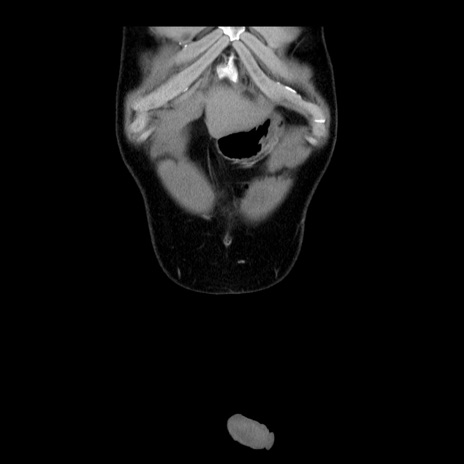

症例4(冠状断像)

【症例】30歳代男性

【主訴】腹痛、嘔吐

【現病歴】昨晩から突然の腹痛あり、その後嘔吐、軟便も出現。腹痛が改善しないため救急搬送となる。2日前にしめ鯖の食事歴あり。

【身体所見】意識清明、苦悶様、BP 135/90mmHg、BT 35.7℃、腹部:平坦、やや硬、心窩部〜臍部に自発痛、圧痛あり、筋性防御+、反跳痛-

【データ】WBC 8100、CRP 0.57